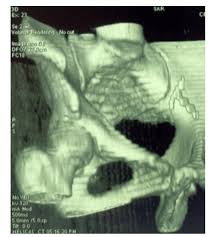

Us confirmed proper placement of the iud. Would it be proper for me to use the 58562 code although the iud was not technically embedded. Subsequently, question is, how do i know if my insurance covers my iud? She presents today for the removal of her iud due to (desire for pregnancy/abnormal bleeding/pain/due for removal/other). Note that modifier 51 (multiple procedures) is added to the lesser procedure.

With removal of impacted foreign body)for the removal of the iud and diagnosis code 996.32 (mechanical complicaion due to intrauterine contraceptive device).